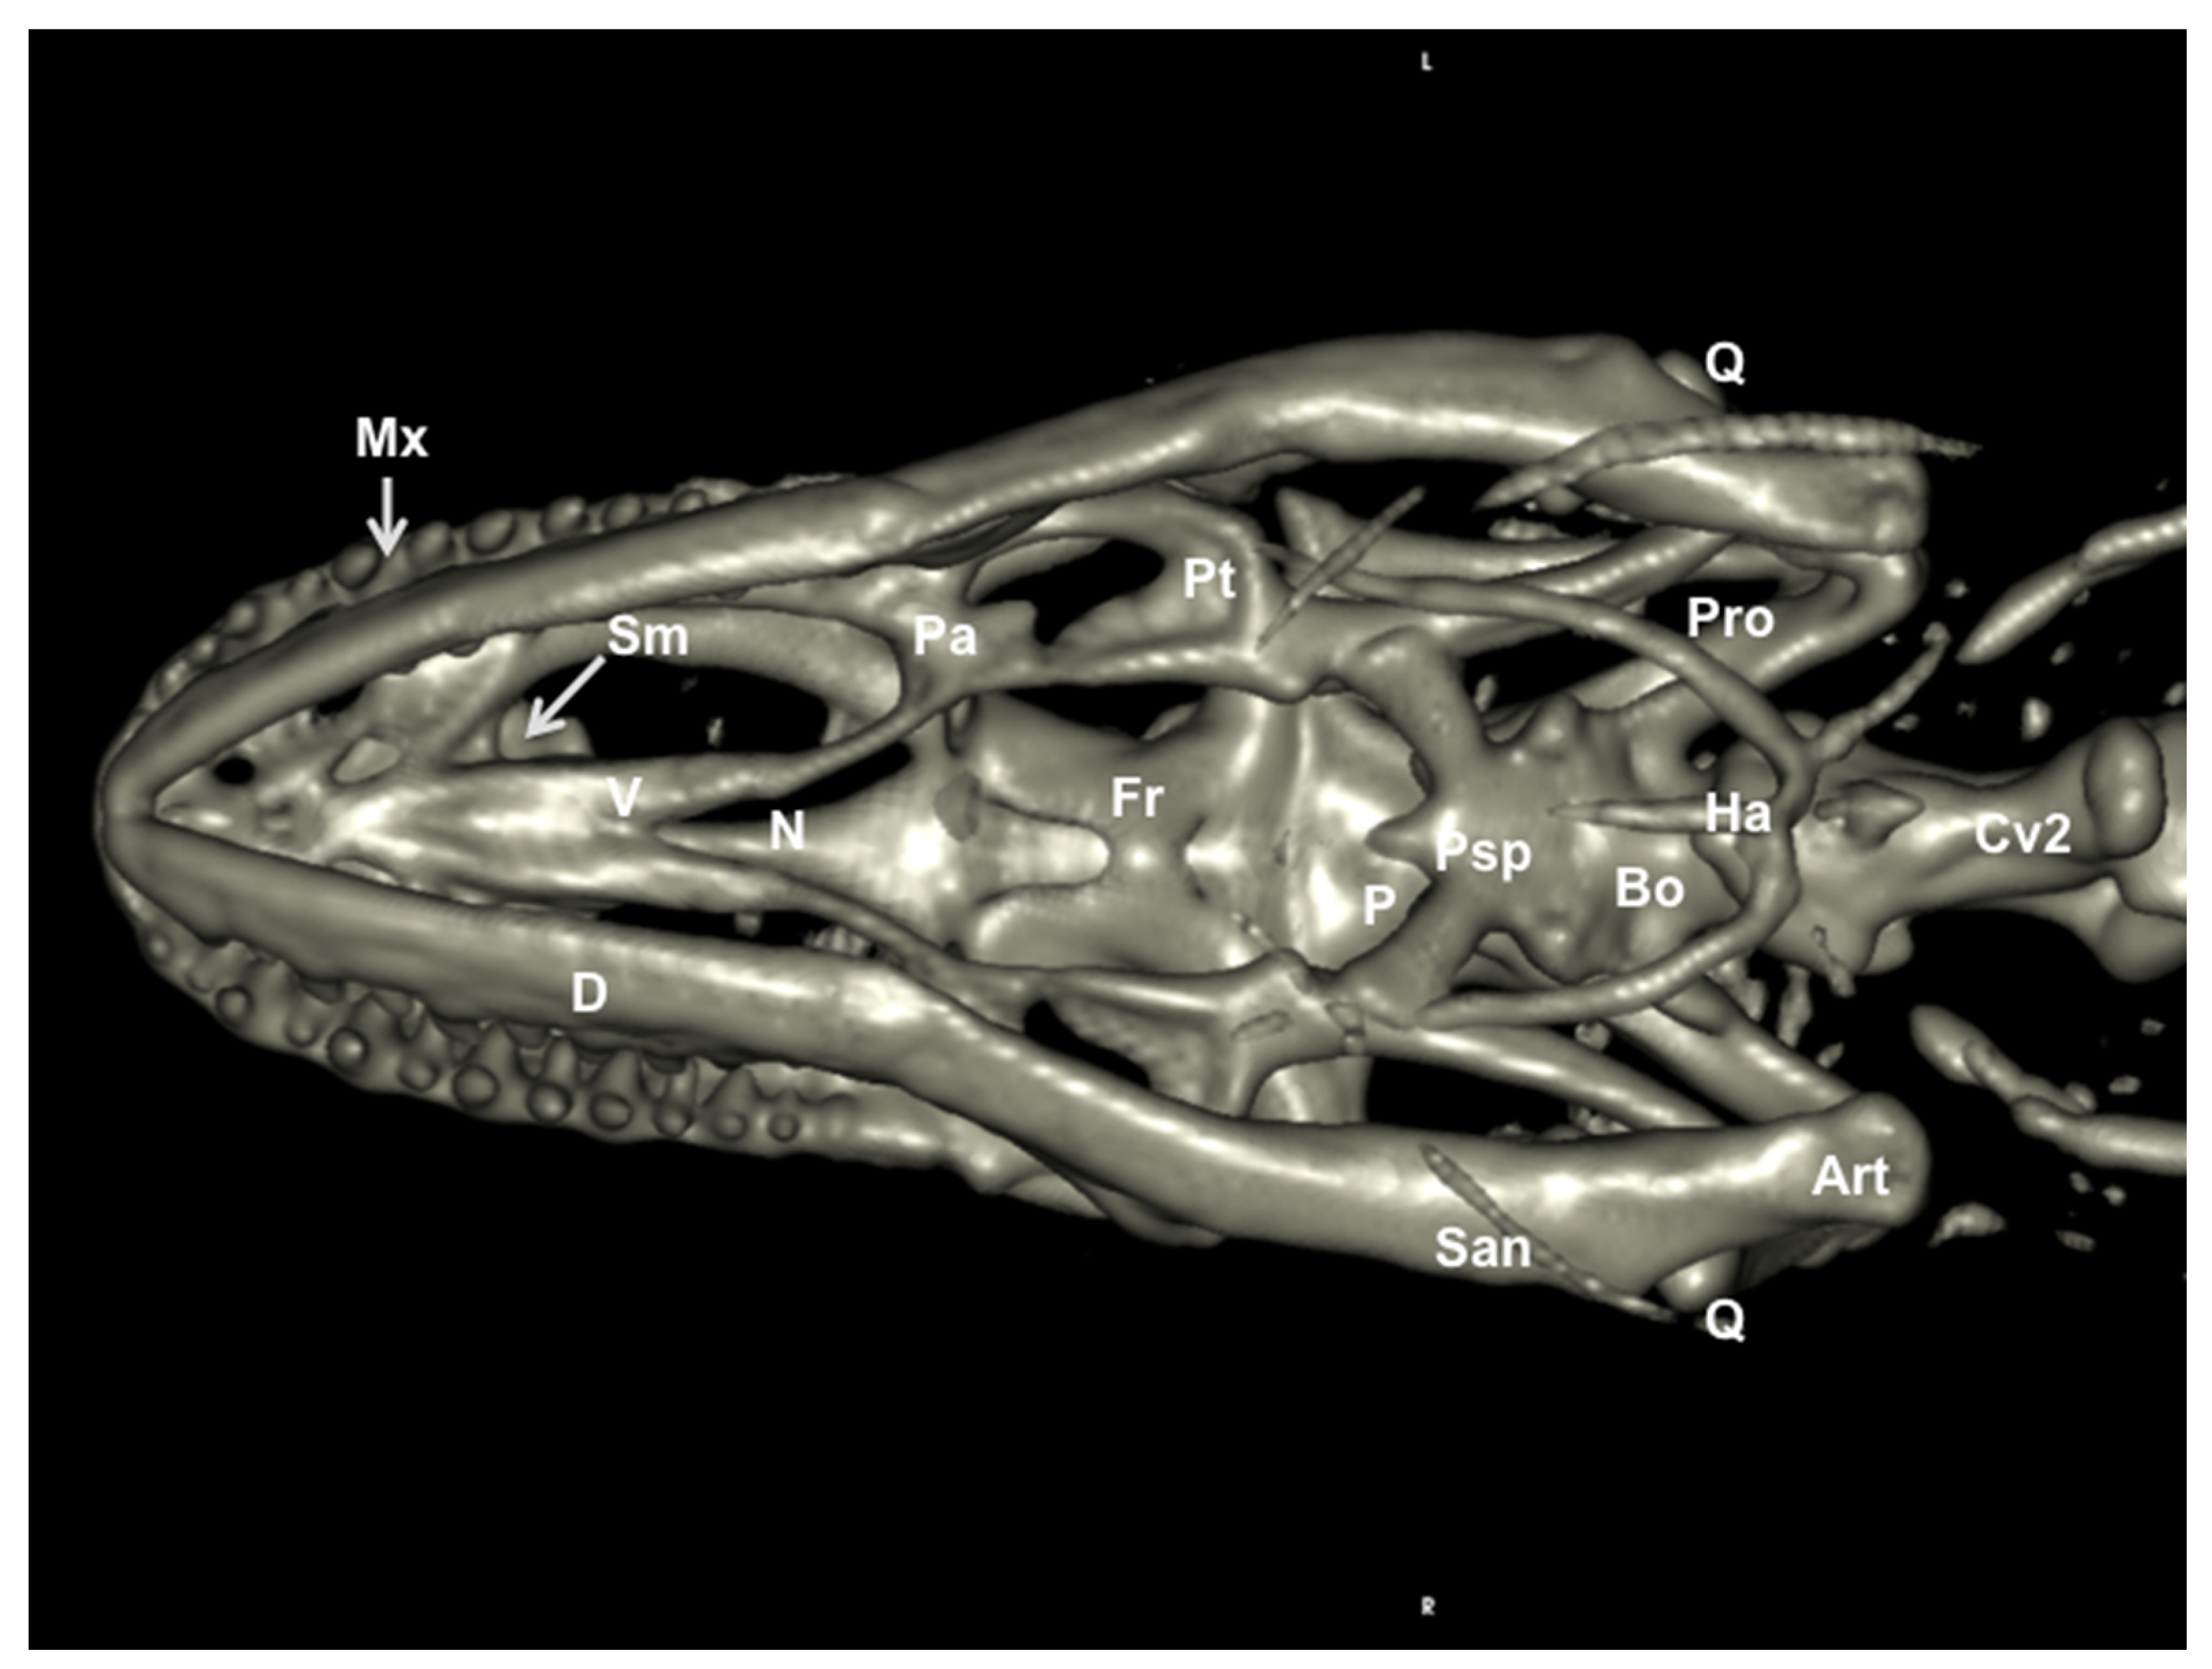

3.2. Head Volume-Rendered Reconstructed Images